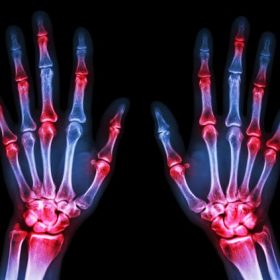

Arthritis, defined as painful inflammation and stiffness of joints, affects an estimated 54.4 million adults in the U.S. every year.6 There are over 100 different types of arthritis, the most common being osteoarthritis, rheumatoid arthritis, lupus, and fibromyalgia.

Rheumatoid arthritis is a chronic inflammatory disease. It is characterized by excess fluid and buildup of free radicals in the joint. Free radicals cause “oxidative stress” in the body. When there is an imbalance between antioxidants and free radicals, oxidative stress occurs. Your body is not able to cleanse itself of toxins.